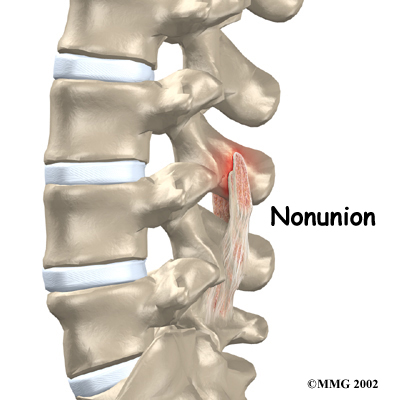

Nonunion

Sometimes the bones do not fuse as planned. This is called a nonunion, or . (The term pseudarthrosis means false joint.) When more than one level of the spine is fused at one time, there is a greater chance that nonunion will occur. Fusion of more than one level means that two or more consecutive discs are removed and replaced with bone graft. If the joint motion from a nonunion causes pain, you may need a second operation.

In the second procedure, the surgeon usually adds more bone graft. Metal plates and screws may also be added to rigidly secure the bones so they will fuse together.